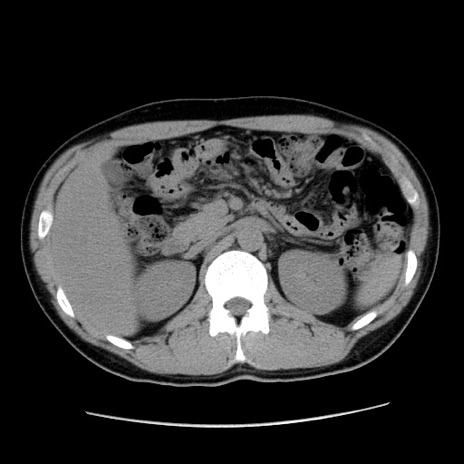

症例36(横断像)

【症例】20歳代 男性

【主訴】心窩部痛

【現病歴】今朝より上腹部痛あり。一旦軽快していたが再度出現したため救急要請。昨日夕に白身の魚を含む刺身を食べた。

【身体所見】BP 136/89mmHg、HR 74/min、BT 37.0℃、腹部:膨満、軟、心窩部に圧痛あり。反跳痛なし、筋性防御なし、腸雑音やや亢進あり。

【データ】WBC 17700、CRP 0.48